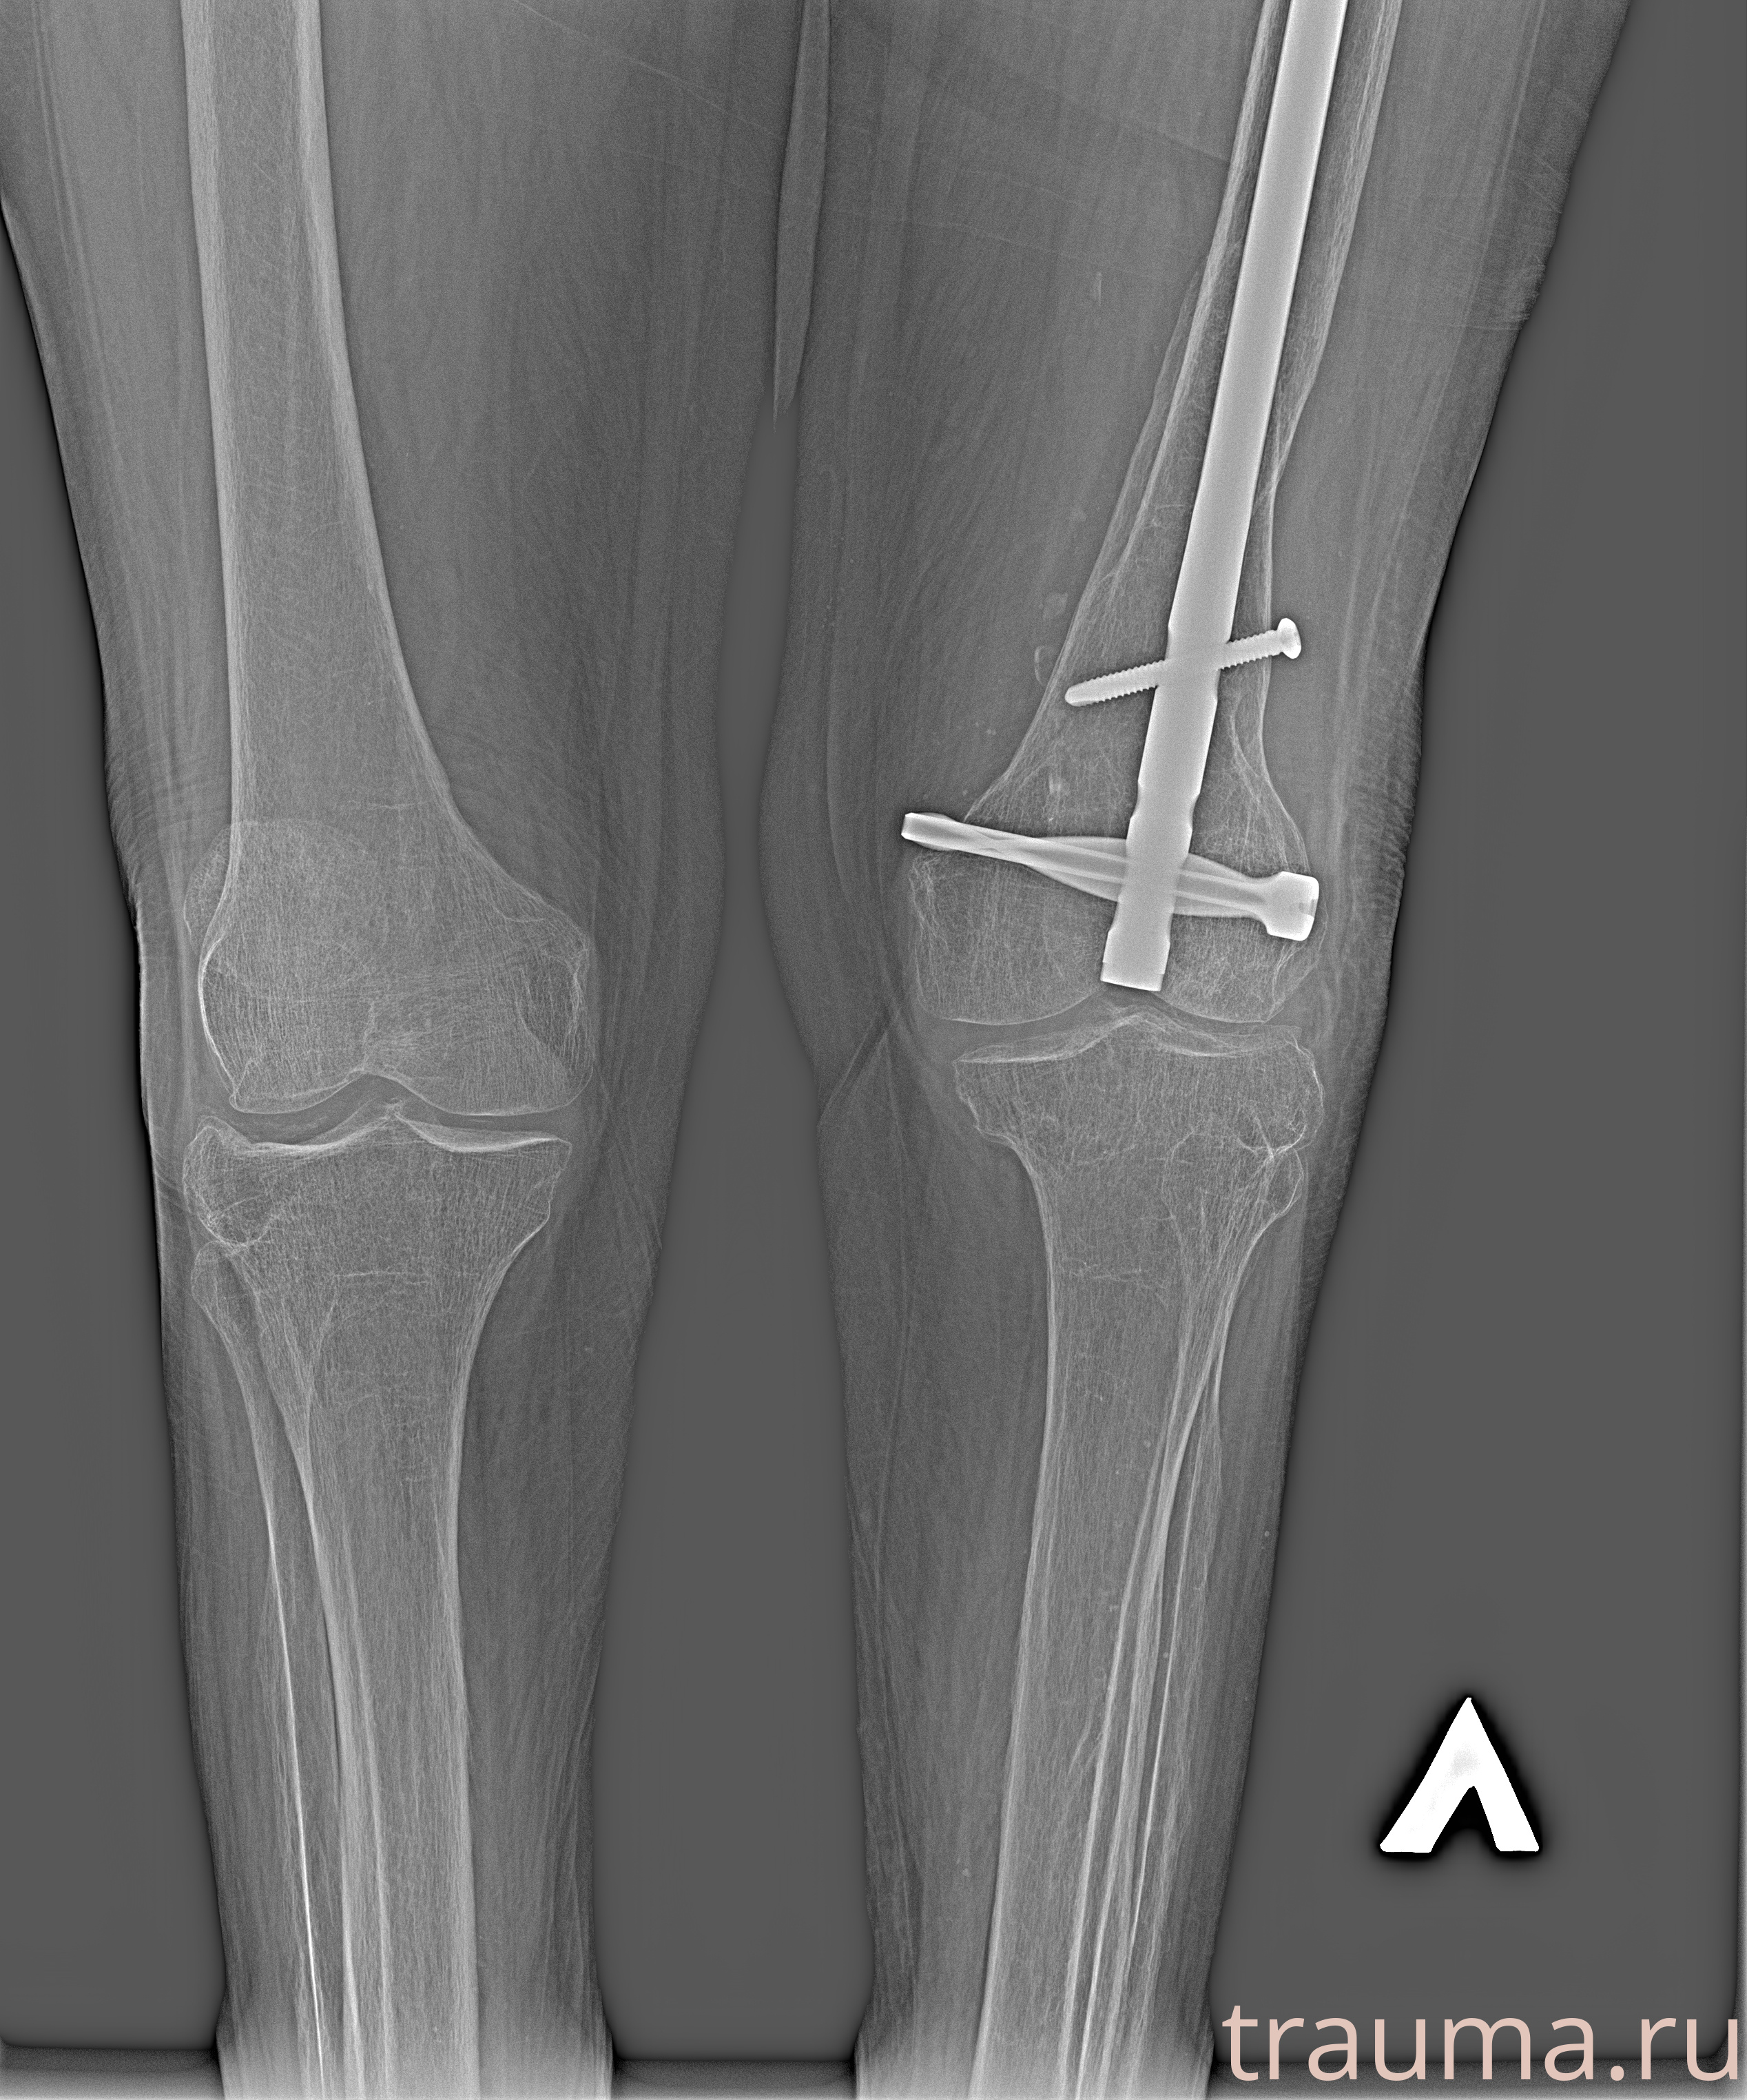

Перелом 3-5 ребер слева

Рентген на дому: по вашему адресу приезжает врач-рентгенолог, травматолог-ортопед с мобильным рентгеновским аппаратом, проводит диагностику травмы или заболевания, делает необходимые рентгенограммы, дает рекомендации по дальнейшему лечению. Получить качественные снимки в домашних условиях возможно благодаря уникальной методике, разработанной МосРентген Центром для института  Склифосовского